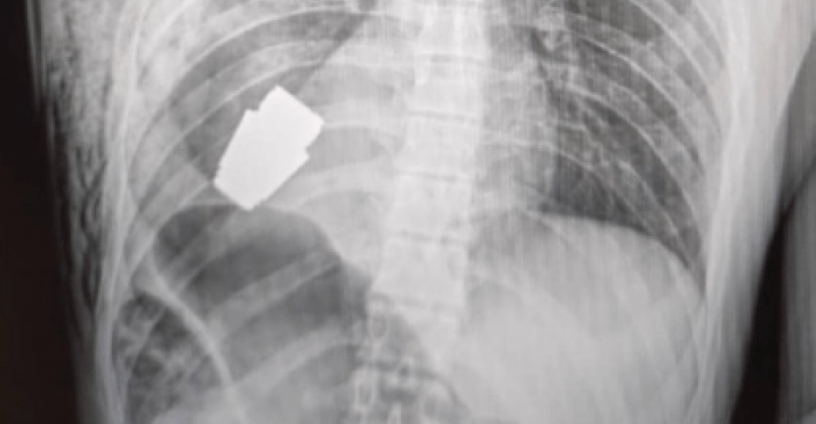

En esa mismo mensaje, el asesor ministerial publica dos fotografías: una de una radiografía que muestra la granada incrustada en el lado derecho del pecho del soldado y otra del cirujano, ya con el artefacto en la mano.

El artefacto, que parece ser de tipo VOG-25, es un lanzagranadas acoplado ruso, apodado «hoguera», que se usa para los fusiles de asalto de la serie Kalashnikov.